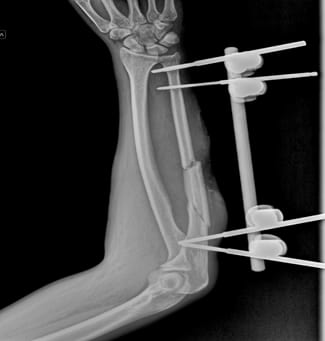

Вначале доктора хирургически обработали рану раны с пластикой местными тканями и установили аппарат КСВП (для быстрой чрезкостной фиксации переломов трубчатых костей) на локтевую кость предплечья.

Через две недели провели кожную пластику, где использовали расцепление кожного лоскута. Такую процедуру применят для заживления обширных ран.